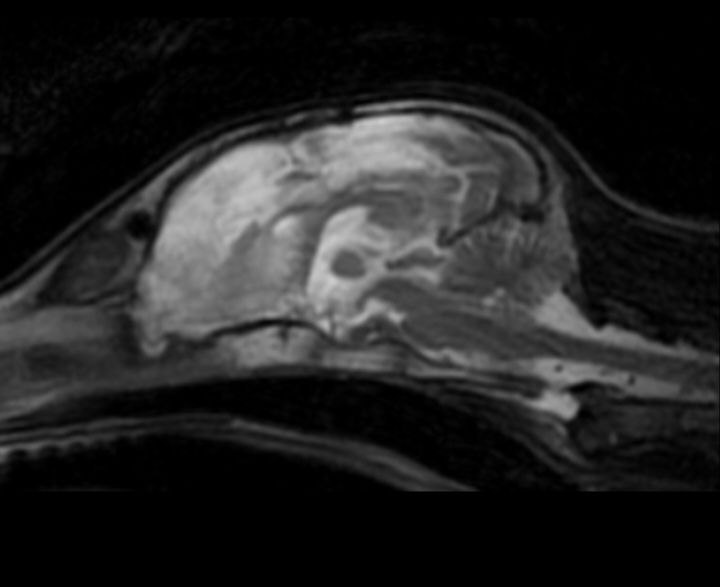

Пациент: 4-месячный щенок (метис). Субдуральная гематома, возникшая в результате закрытой черепно-мозговой травмы (ЗЧМТ). В данном случае с целью устранения гематомы и предотвращения дальнейшего сдавления мозговых структур была выполнена краниотомия.В связи с изменениями, опосредованными ЗЧМТ и смещением структур головного мозга вправо, возникла необходимость пересмотра плана проведения операции и возможного расширения хирургического доступа у данного пациента. Для обеспечения адекватной анальгезии пациента было принято решение о проведении блокады тройничного нерва (рис. 23, 24).

У данного пациента не было выявлено отклонений в показателях витальных функций на протяжении всего оперативного вмешательства. Единственным исключением стало гемодинамически незначимое снижение ЧСС на 20–30% после завершения доступа к головному мозгу, которое обусловлено вегетативными реакциями нервной системы. Ввиду сохранения продуктивного спонтанного дыхания ИВЛ данному пациенту не проводилась. В ходе операции и в раннем послеоперационном периоде системное применение анальгетиков не потребовалось (рис. 25).

Пациент был выписан из ОРИТ спустя 72 ч. после завершения оперативного вмешательства.